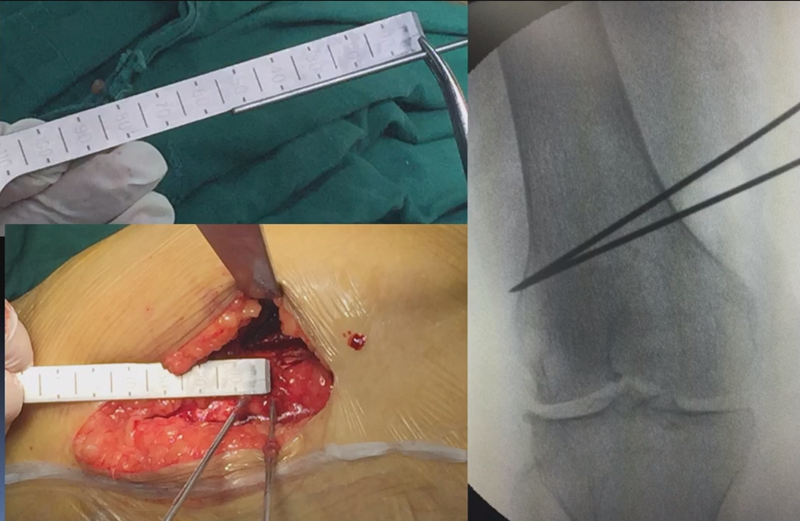

术前推荐用力线杆核实力线,通常在术前计划时,需要做下肢全长片,但是有些医院的下肢全长片为拼接而来,可能会存在拼接误差,继而影响术前计划的准确性,因此推荐术前再次使用力线杆评估力线,以保证与术前计划一致。

合页点和截骨线已确定好,按照术前计划打入导针,测量截骨深度。